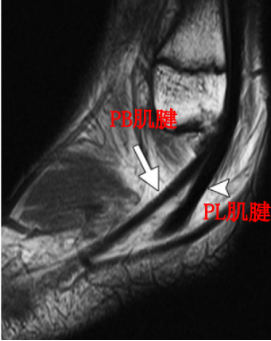

腓骨长肌(PL):起于腓骨头、腓骨外侧面上2/3和小腿深筋膜,止于第1跖骨外侧及毗邻的第1楔骨的内侧,至小腿下1/3处,长肌移行为肌腱,在它到达止点前的行程中有三个弯曲,第一个在外踝顶点,第二个在跟骨外侧壁的腓骨肌滑车下,第三个在骰骨结节处经90°转到足底。

腓骨短肌(PB):起于腓骨外侧面下2/3及前后肌间隔,短肌至外踝的后下方始为移行为肌腱,紧贴于外踝后方,通过外踝顶点转向足外侧前方,经过跟骨外侧壁腓骨肌滑车上方最后止于第五跖骨基底。

MRI:能更清楚地显示软组织损伤情况,如支持带撕裂和腓骨肌腱半脱位。对于指导临床治疗及后期随访观察疗效具有重要参考价值。